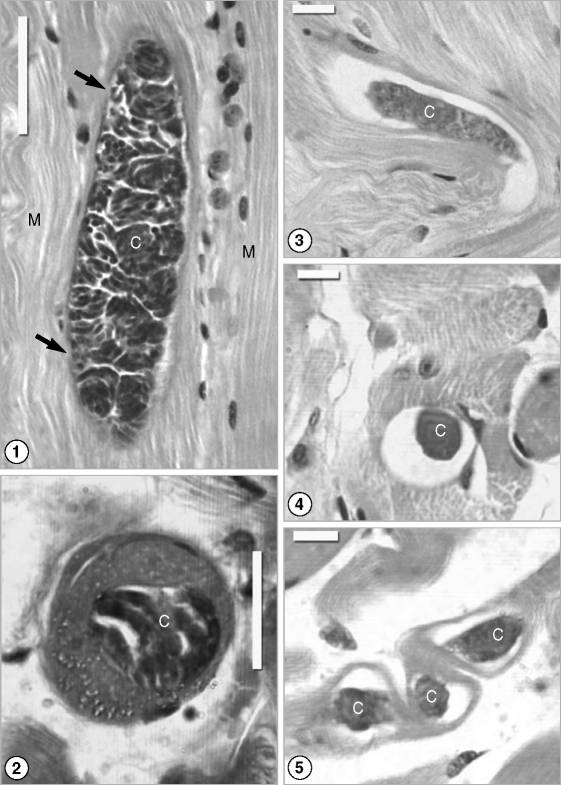

Light microscopy